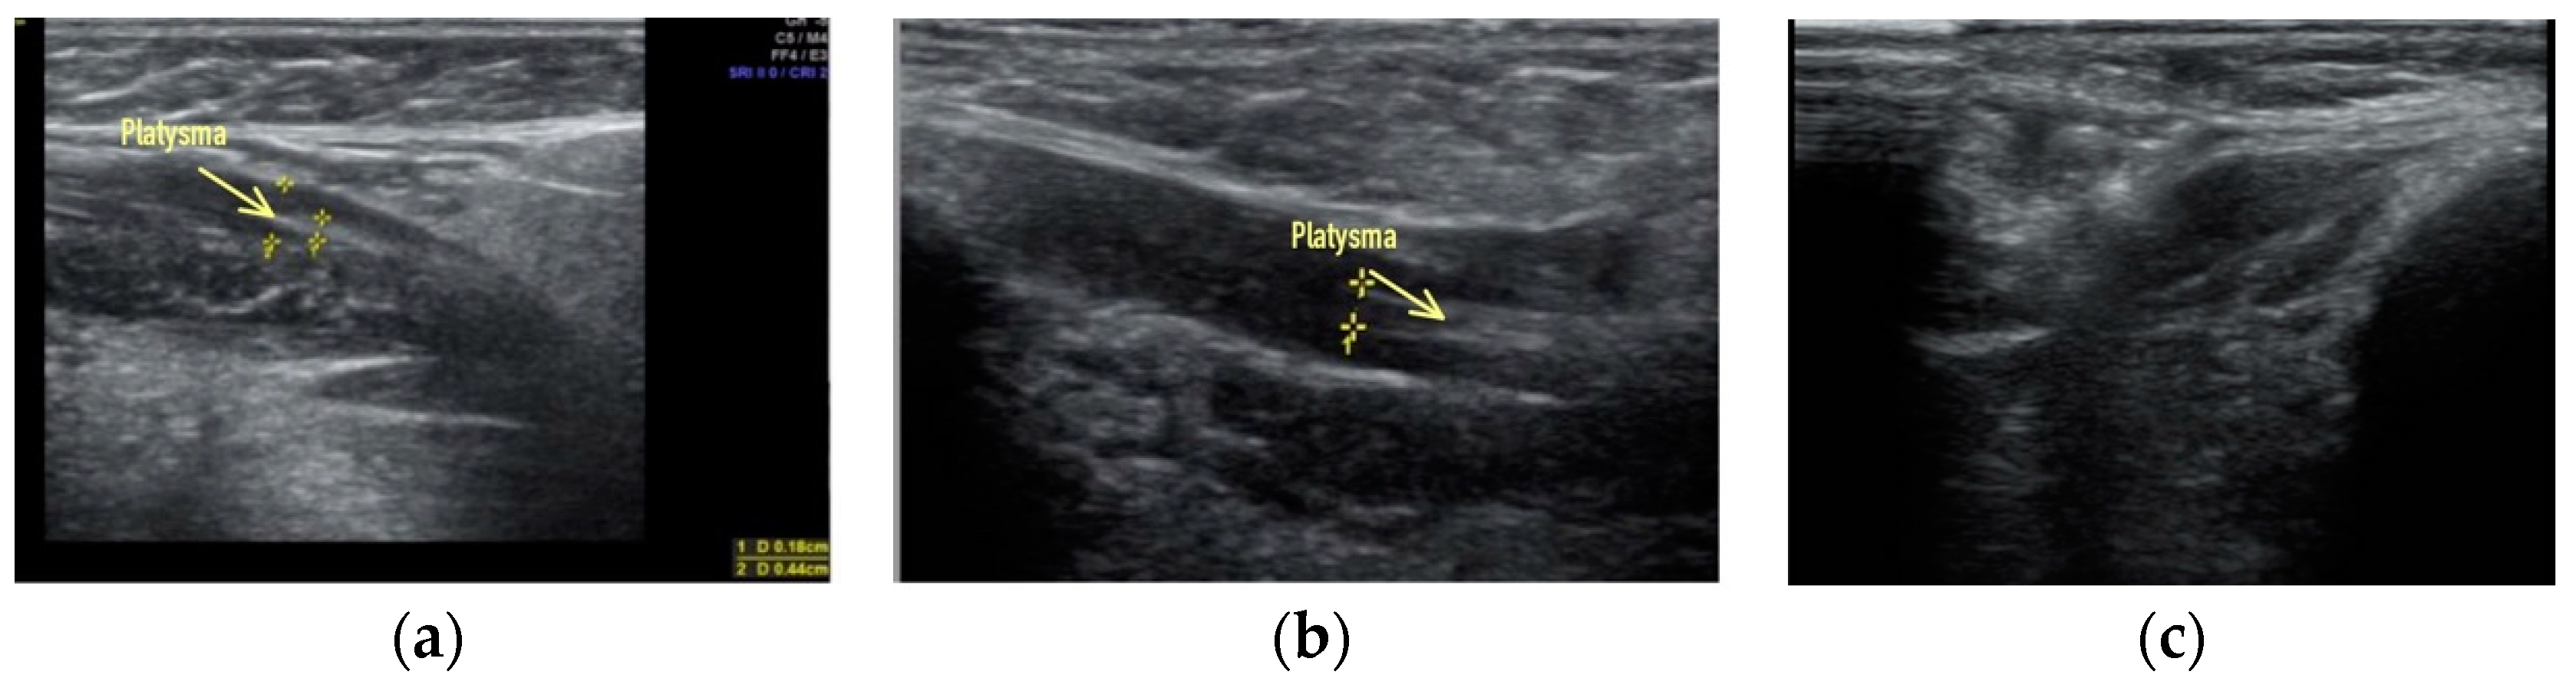

Clinical case #2. During the study, a 52-year-old female patient with a 15 MHz linear transducer of soft tissues of the lower third of the face and neck without pressure, in an upright position, displayed sagging platysma and the presence of cords on two sides (Figure 2a,b) as well as a slight accumulation of adipose tissue in the chin area (Figure 2c).

Figure 2.

B-mode ultrasound examination of the soft tissues of the lower third of the face and neck with a 14 MHz linear transducer. Sagging of the platysma, strands (a,b), and a slight accumulation of adipose tissue in the submental area (c).

According to the results of ultrasound examination, it is obvious that a radical improvement in the contours of the neck–submandibular angle will not be achieved by acting only on the adipose tissue; correction of ptotic platysma is also necessary in this clinical case.